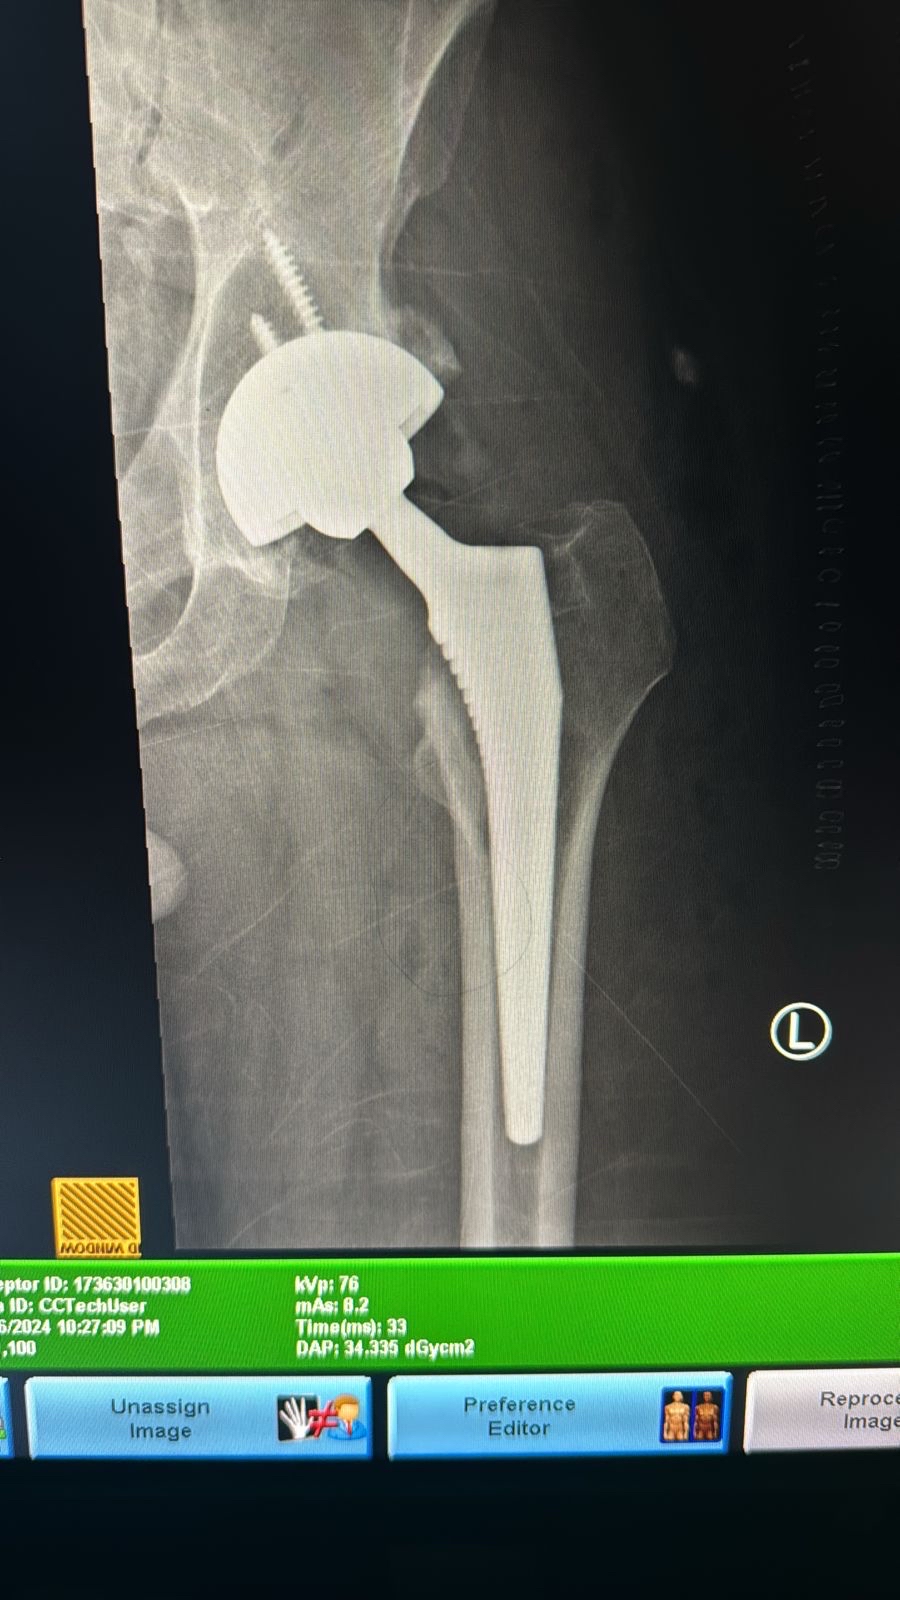

أجرى فريق طبي متخصص في جراحة العظام والمفاصل بمجمع الدمام الطبي، التابع لشبكة الدمام الصحية، عملية استبدال مفصل الورك لمريض عماني، يبلغ من العمر 52 عامًا، ويصل طوله إلى أكثر من مترين.

وأوضح استشاري جراحة العظام المتخصص في تبديل المفاصل وكسور الحوادث المعقدة د. عبدالعزيز البراك، أن العملية الجراحية استغرقت ساعتين، تم خلالها تركيب المفصل الصناعي بنجاح، وكانت العملية تمثل تحديًا كبيرًا بسبب حجم المفصل الصناعي الكبير الذي يتناسب مع طول المريض البالغ مترين وبنيته الجسمانية الضخمة.